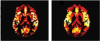

Partial volume correction using modified least trimmed squares (PVC-mLTS) is a software toolbox that can be employed to correct partial volume effect for single inversion-time ASL data.

(3) Computing CBF maps for both GM and WM.